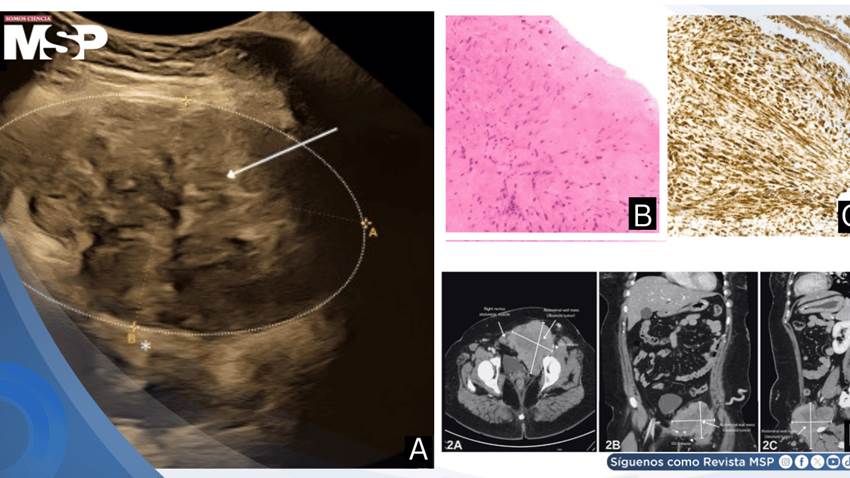

El examen ultrasonográfico demostró una masa heterogénea considerable en la pared abdominal izquierda que medía 10.7 por 6.5 por 10.6 centímetros. La lesión se originaba en el músculo recto abdominal izquierdo con posible extensión hacia el lado contralateral en su porción inferior, sin evidencia macroscópica de invasión intraperitoneal. Los estudios Doppler venosos confirmaron la presencia de trombosis venosa profunda crónica extensa desde la vena ilíaca izquierda hasta la vena poplítea.

La evaluación exhaustiva en el período posparto incluyó tomografía computarizada de abdomen completo con contraste endovenoso, que documentó un incremento del tamaño tumoral a 10.1 por 10 por 9.5 centímetros.

Las imágenes demostraron una masa heterogénea en la pared abdominal inferior izquierda con compromiso bilateral de los músculos rectos abdominales, extensión al músculo psoas izquierdo, obturador interno y pectíneo, con infiltración hacia el canal inguinal.

Significativamente, se confirmó invasión de la vena ilíaca externa izquierda y la vena femoral común, además de identificarse un ganglio linfático inguinal ipsilateral levemente aumentado de tamaño.

La biopsia guiada por ultrasonido proporcionó el diagnóstico histopatológico definitivo. El análisis microscópico con tinción de hematoxilina y eosina reveló una lesión mal circunscrita compuesta por células fusiformes con núcleos alargados y cromatina fina, organizadas en fascículos entrelazados dentro de un estroma colagenoso abundante.

Se observaron figuras mitóticas escasas sin evidencia de atipia citológica significativa ni necrosis tumoral. El estudio inmunohistoquímico demostró positividad citoplasmática difusa e intensa para vimentina en todas las células tumorales fusiformes, hallazgo compatible con el diagnóstico de fibromatosis tipo desmoide.